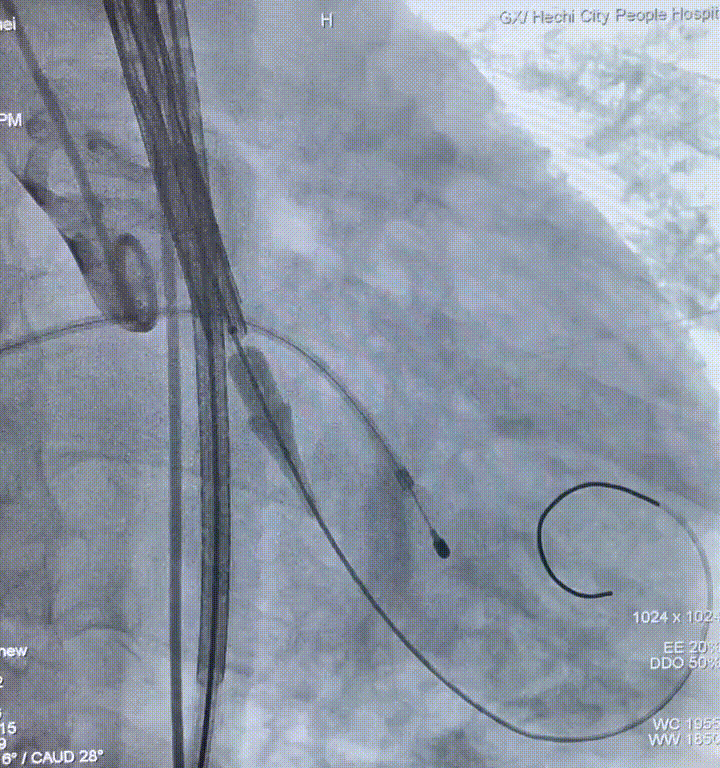

二尖瓣球囊扩张

瓣膜定位

瓣膜释放

瓣膜释放至可回收极限位

释放完成

人工瓣膜在主动脉瓣处锚定释放后,工作正常,造影未见瓣周漏,零压差,二尖瓣瓣口面积从0.55cm²恢复至1.2cm²以上,患者血流动力学得到明显改善,手术圆满完成,患者苏醒后顺利转入病房。

此案例中,唐秀革院长、莫昌干主任手术团队先为患者施行PBMV,再借助VitaFlow Liberty™电动可回收瓣膜输送系统进行TAVR,术后造影检查和心脏彩超评估人工瓣膜位置佳,活动良好,主动脉瓣跨瓣压差为零,无瓣周漏现象。患者心功能得到显著改善,手术取得圆满成功。此次手术的成功开展彰显了TAVR治疗主动脉瓣反流的安全性和有效性,也表明河池市人民医院心脏瓣膜团队手术技术的不断精进与成熟,为辖区内高龄、复杂心脏瓣膜疾病患者带来了治愈的希望。